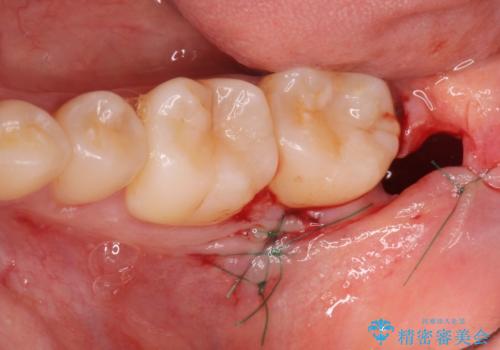

親知らず・埋伏歯の抜歯掲載症例数39件

最新 親知らず・埋伏歯の抜歯症例